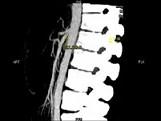

问题 女,24岁,发作性肉眼血尿1年,实验室检查:尿蛋白(-+)、红细胞(12/HP),尿蛋白直立试验(+),CT扫描如图,下列说法正确的是 ( )

选项 A.双肾大小形态正常 B.左肾静脉走行至肠系膜上动脉与腹主动脉间变细,近左肾处扩张 C.左侧肠系膜上动脉与腹主动脉夹角变小 D.左侧肠系膜上动脉与腹主动脉夹角增大 E.考虑为左肾静脉胡桃夹综合征

答案 ABCE